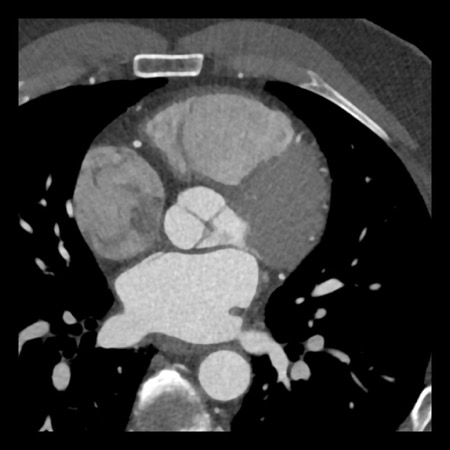

case 1 – CAD-RADS 2/P1

First, scroll through the scan.

Not all images are included. Some images without any abnormalities are skipped

from the series.

How would you describe the findings on the coronary CTA?

The findings are:

- Agatston score of

this patient was 14 (P1). Please, also note the calcification of the aortic valve. - Some partially

calcified and calcified plaques are present in the LAD with mild stenosis

(25-49%). - Calcified-plaque in

the LCX causing minimal stenosis (<25%). - Non-calcified

plaque in the distal RCA causing minimal stenosis (<25%). - This patient classifies

as CAD-RADS 2/P1, which means no further workup is needed.